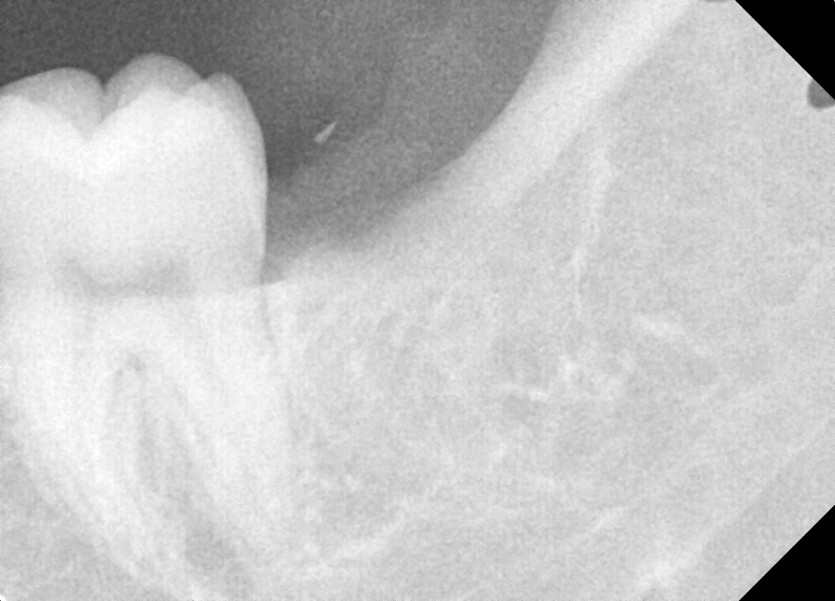

#28,38 사랑니 발치

구강 외과 전문의가 당일 발치했습니다.